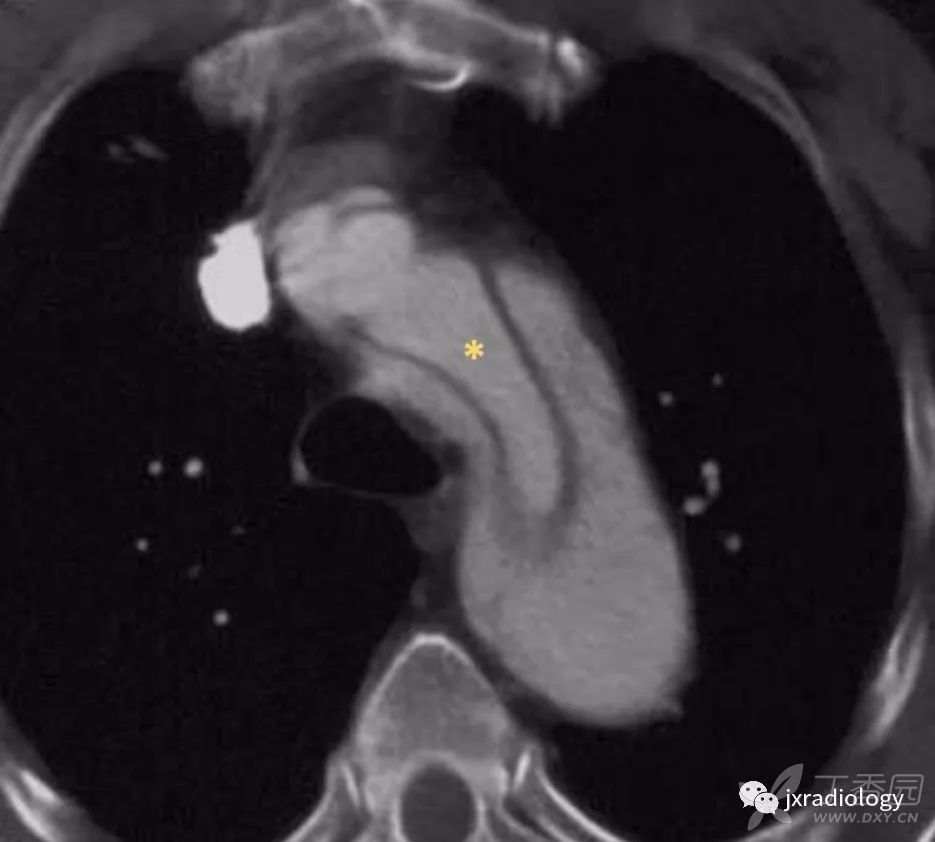

图8:鸟嘴征(箭头)代表假腔。

它是指在假腔内扩张的楔形血肿,因为它可以占据空间并分离内膜。真腔(星号)可通过其较小的管腔和早期强化来与假腔区分。